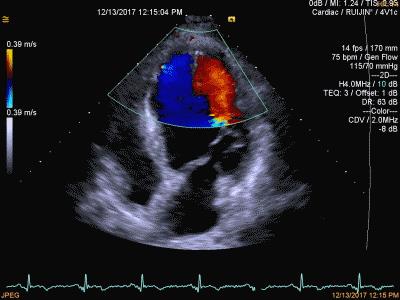

D型:是专门用来检测血液流动和器官活动的一种超声诊断方法,又称为多普勒超声诊断法。可确定血管是否通畅、管腔有否狭窄、闭塞以及病变部位。

D型--彩色多普勒超声诊断仪

D型超声诊断法即多普勒法 图 心脏彩超

新一代的D型超声波还能定量地测定管腔内血液的流量。近几年来科学家又发展了彩色编码多普勒系统,可在超声心动图解剖标志的指示下,以不同颜色显示血流的方向,色泽的深浅代表血流的流速。现在还有立体超声显象、超声CT、超声内窥镜等超声技术不断涌现出来,并且还可以与其他检查仪器结合使用,使疾病的诊断准确率大大提高。超声波技术正在医学界发挥着巨大的作用,随着科学的进步,它将更加完善,将更好地造福于人类。